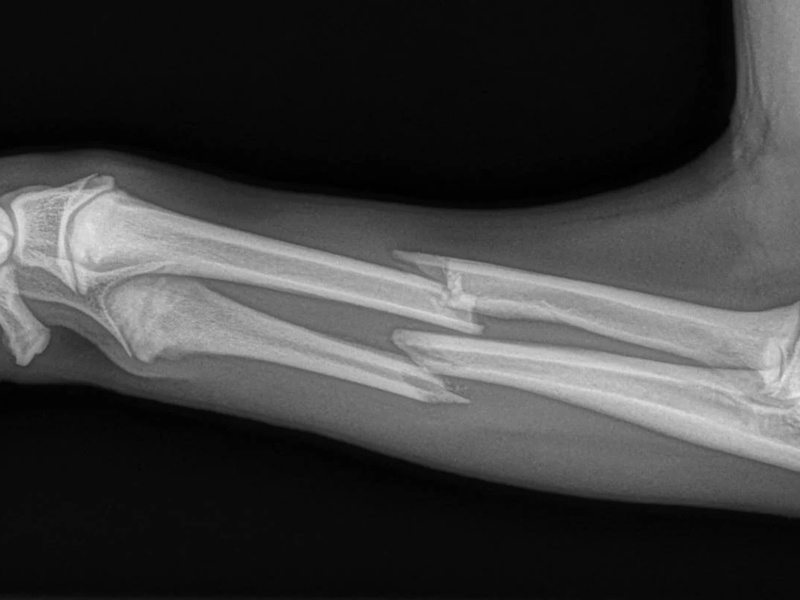

Fore Limb (Humerus, Radius/Ulnar, Metacarpus)

Hind Limb (Pelvis, Femur, Patella, Tibia/Fibula, Lateral Malleolus)

- Fracture Fixation: $4,000 - $8,000+